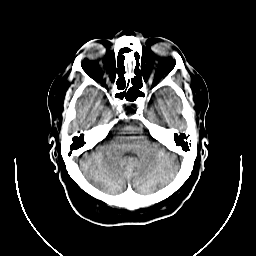

CT Study #1 -- Slice #7